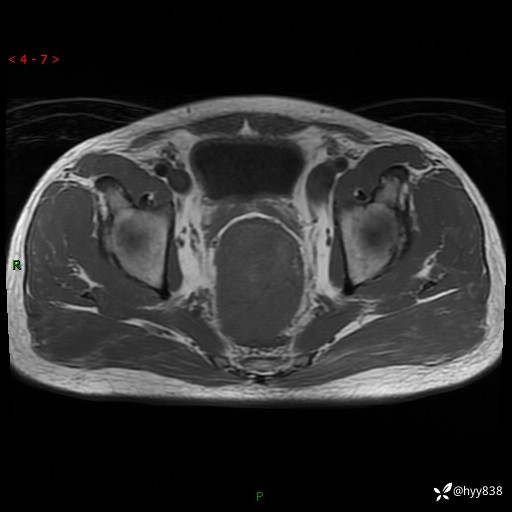

盆腔MRI平扫